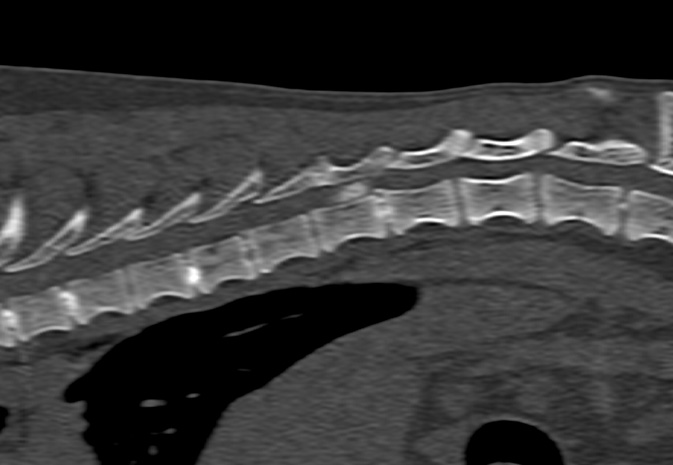

Spinal

Intervertebral Disc Disease

Thoracolumbar Hemi-Laminectomy

Ventral Slot

Dorsal Laminectomy

Spinal Stabilisation

CT Scans